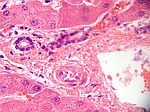

Schockleber, HE